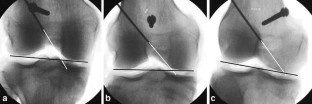

Correct placement of the tibial and femoral bone tunnel is prerequisite to a successful anterior cruciate ligament (ACL) reconstruction. This study compares the resulting radiographic femoral bone tunnel position of two commonly used techniques for arthroscopically assisted drilling of the femoral bone tunnel: the transtibial approach or drilling through the anteromedial arthroscopy portal. The resulting bone tunnel position was assessed in postoperative knee radiographs of 70 patients after ACL reconstruction. Three independent observers identified the femoral bone tunnel and determined its position in the lateral and A–P view. Differences in femoral tunnel position between transtibial and anteromedial drilling were evaluated. In the sagittal plane, significantly more femoral bone tunnels were positioned close to the reference value using an anteromedial drilling technique (86%) when compared to transtibial drilling (57%). Drilling through the transtibial tunnel resulted in a significantly more anterior position of the femoral tunnel. In the frontal plane, femoral bone tunnels which were placed through the anteromedial arthroscopy portal displayed a significantly greater angulation towards the lateral condylar cortex (50.92°) when compared to transtibial drilling (58.82°). In conclusion, drilling the femoral tunnel through the anteromedial arthroscopy portal results in a radiographic femoral bone tunnel position which is suggested to allow stabilization of both anterior tibial translation and rotational instability when using a single bundle reconstruction technique. Further studies may evaluate if there are any clinical advantages using the anteromedial portal technique.

Fig. 2